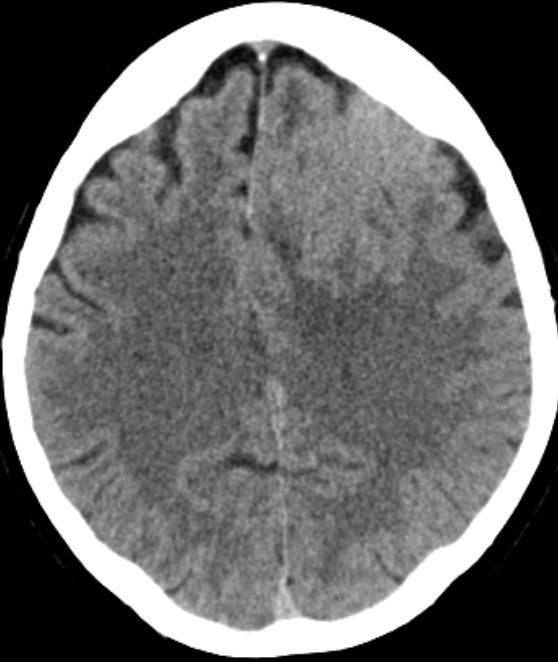

| Meningeom frontal |

59-jähriger Patient, der wegen AV-Block in die Kardiologie eingeliefert wurde. Das CT zeigt einen hirninvasiven Tumor, der die Mittellinie überschreitet. Postoperativ ergab sich ein Meningeom 2. Grades. | . |